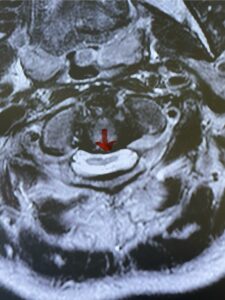

Fig. 4b: Axial T2-weighted cervical MRI demonstrating severe spinal cord compression from atlanto-axial instability (red arrow)